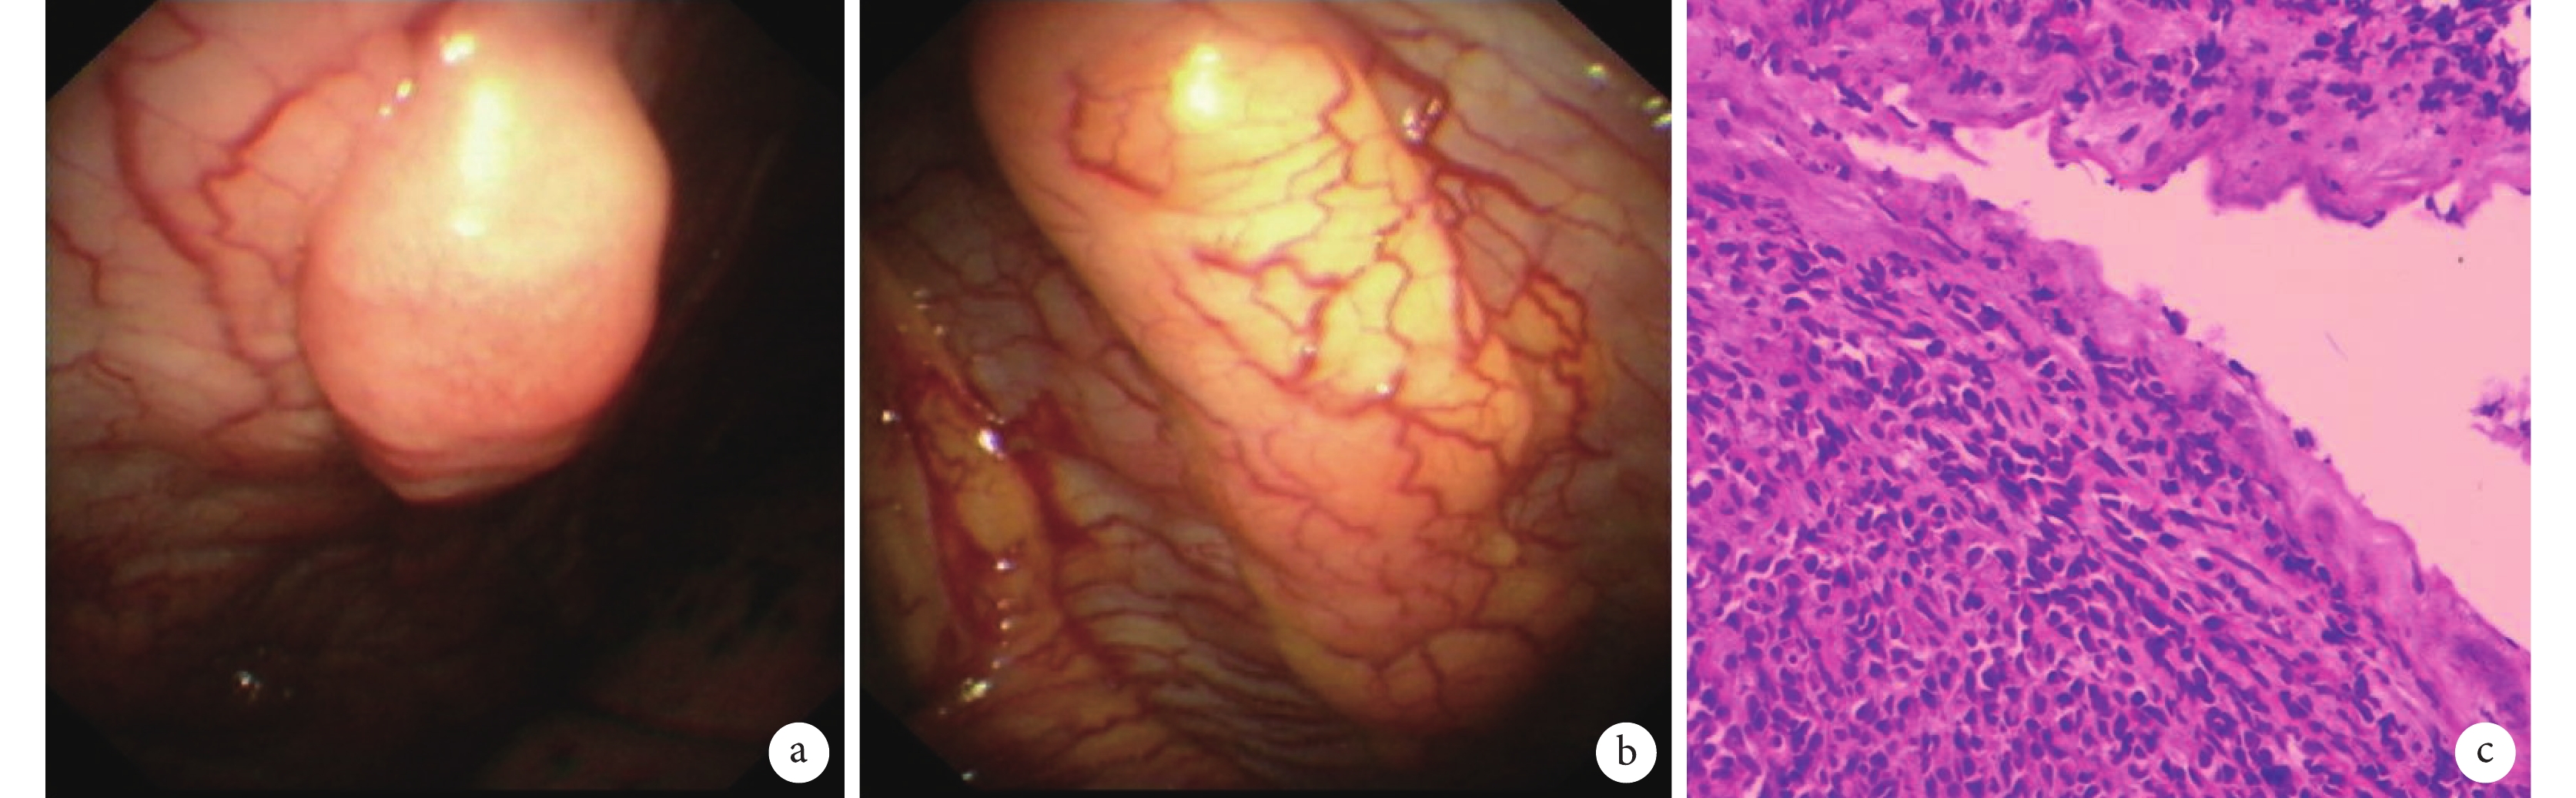

為明確診斷,予行局部麻醉胸腔鏡檢查(local anaesthetic thoracoscopy,LAT)。鏡下見壁層胸膜肥厚,血管擴張、紊亂,部分結節樣增生(圖2a、b),多處活檢送病理檢查。組織病理提示胸膜下漿樣腫瘤細胞彌漫性浸潤。細胞卵圓形,胞質嗜堿性,核偏位,有異型,無明顯核仁,可見病理性核分裂象(圖2c)。結合患者外院胸腔積液沉渣結果,故增加相關免疫組織化學指標。結果如下:瘤細胞波形蛋白(++),結蛋白(–),平滑肌肌動蛋白(–),廣譜細胞角蛋白(–),佛氏白血病病毒整合蛋白1(+),細胞增殖指數Ki67(約30%+),MyoD1(–),成肌蛋白(–),白細胞共同抗原(–),S-100(–),上皮膜抗原(灶+),分化抗原30(cluster of differentiation 30,CD30)(–),CD99(+),間變性淋巴瘤激酶ALK p80(–),CD38(+),髓過氧化物酶(–),間皮細胞(–),D2-40(–),細胞角蛋白(cytokeratin,CK)5/6(–),CK7(–),CD19(–),CD43(–),原位雜交EBV編碼的小RNA(–),Syn(–),嗜鉻粒蛋白A(–),CD56(–),CD138(+),Kappa(–),Lambda(++),CD79a(弱+),多發性骨髓瘤癌基因1(+),符合漿細胞瘤。

a、b. 胸腔鏡檢查像,見壁層胸膜肥厚,血管擴張、紊亂,部分結節樣增生;c. 胸膜結節活檢病理檢查像(蘇木精–伊紅×200),胸膜下漿樣腫瘤細胞彌漫性浸潤。細胞卵圓形,胞質嗜堿性,核偏位,有異型,無明顯核仁,可見病理性核分裂象。